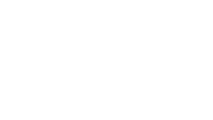

Existem vários quadros de Transtorno Neurocognitivo maior, dentre a mais comum, o Alzheimer. Através de uma avaliação global e aplicação de testes direcionados, o Terapeuta Ocupacional irá detectar funções comprometidas e aquelas ainda preservadas. Bem como aquelas que ainda precisam ser organizadas.

Através de atividades direcionadas ao quadro especifico, o profissional da Tempo e Equilíbrio – Terapia ocupacional, irá intervir diretamente em novas conexões cerebrais e organizar as já existentes, com o objetivo de oferecer uma melhora da independência e autonomia por mais tempo possível, retardando assim, a progressão da doença.

Impacto do Alzheimer no cérebro saudável